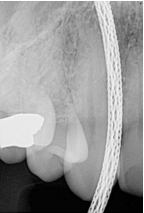

What is the problem with this Wired Cable Issues X-ray?

May occur with direct digital sensors

How would you resolve this Wired Cable Issues X-ray?

Always ensure the cable is not placed between the sensor and source of radiation